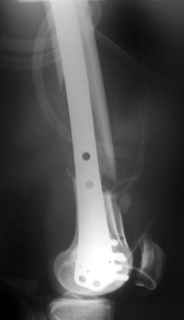

Re: Open supracondylar femur fx

This is what we have done... As generally true for LISS look at the bone not the hardware.

There are two more srews above. The one not completely in got damaged head.

Zsolt